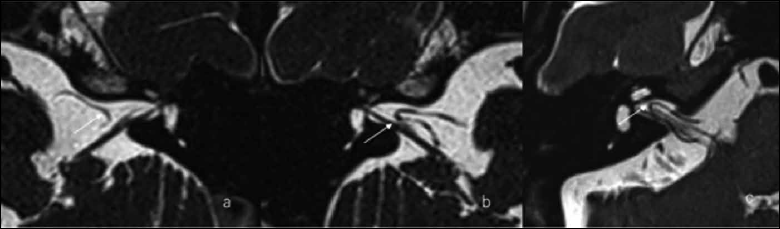

All MRI data were transferred to a workstation and imaging analyses were performed on a picture archiving and communication system (PACS) workstation (Carestream Client, Carestream Health). The MRI data of all patients were intermixed and reviewed by two senior neuroradiologists (L.P with more than ten years of experience and C.C with more than 5 years of experience) who were blinded to the clinical data. This study adopted Chavda 14, Gorrie 15 and Kazawa 16 classification systems. A detailed description of these systems is shown in Table I. Typical examples of AICA variants assessed by the Kazawa, Chavda and Gorrie systems are seen in Figures 1, 2 and 3, respectively.

Figure 2. Chavda classification of AICA loop. (a) AICA loop (arrow) observed in CPA outside the IAC which is type I; (b) Type II in which AICA loop (arrow) is occupying no more than 50% of IAC; (c) Type III in which AICA loop (arrow) leaches more than 50% of total length of IAC.

Figure 3. Gorrie classification of AICA loop. (a,e) AICA loop (A) running separate from cranial nerve (B,C) which is type A; (b,f) Type B in which the AICA loop (A) is running adjacent to the cranial nerve (B,C); (c,g) Type C in which the AICA loop (A) runs between the 7th (C) and 8th (B) cranial nerve; (d,h) Type D in which the AICA loop (A) displacing the nerve resulting in bowing of the nerve (B).